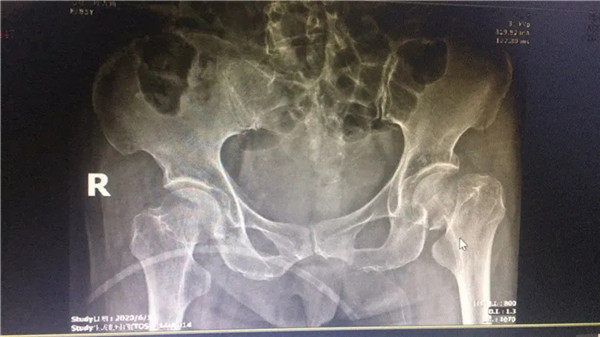

術(shù)前

經(jīng)拍片顯示,陳阿婆左側(cè)股骨頸骨折,須入院手術(shù)治療。一聽要手術(shù),家人便不禁擔(dān)憂起來,這么大年紀(jì)動手術(shù),身體吃得消嗎?危立軍副院長解釋道:高齡病人股骨頸骨折臥床,會導(dǎo)致一系列嚴(yán)重的并發(fā)癥,如疼痛,肺炎、血栓、泌尿系感染等等。隨便哪一項發(fā)生,對病人都是致命打擊,如果病人身體情況不是很差,還是建議進(jìn)行手術(shù),人工關(guān)節(jié)置換,能讓病人盡早恢復(fù)患肢活動,縮短臥床時間,降低死亡率及其他并發(fā)癥的發(fā)生幾率。在聽了危副院長的介紹后,家人遂即辦理了住院手續(xù)。